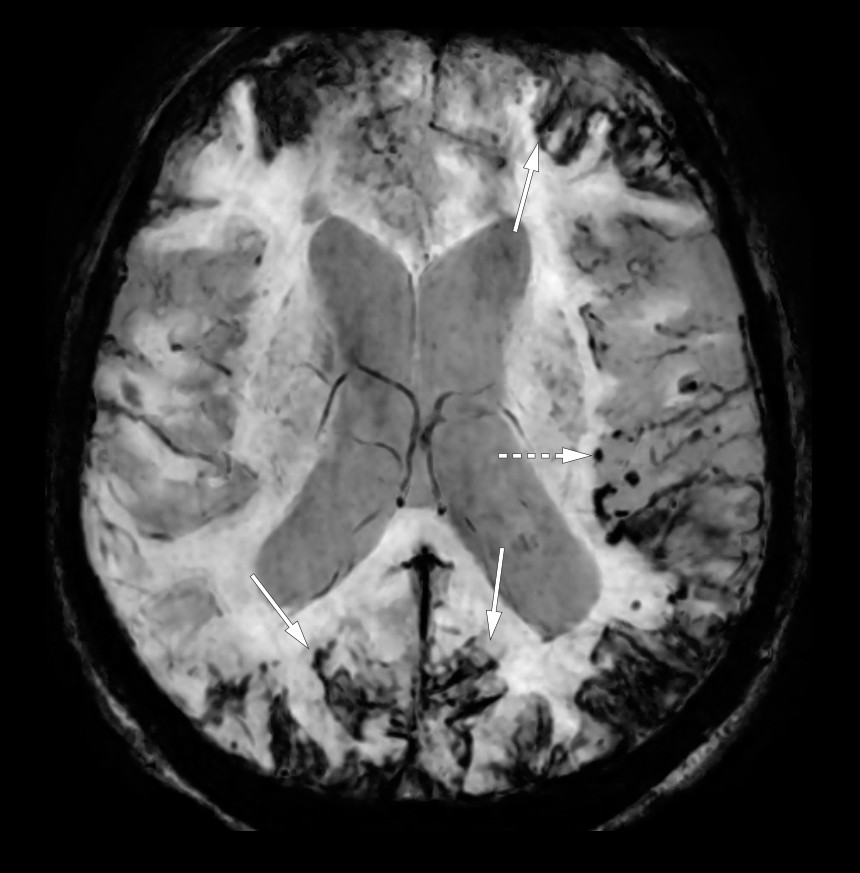

Susceptibilitetsvektede MR-bilder i aksialplanet viste utbredte hemosiderinavleiringer på hjerneoverflaten (heltrukne piler) forenlig med superficiell hemosiderose, tallrike mikrohemoragier i hjerneparenkymet (stiplet pil), de fleste subkortikalt i venstre hemisfære. Mikrohemoragier i forbindelse med en tidligere blødning er typisk for en amyloid angiopati.

Overfladisk hemosiderose av den «klassiske typen» er en sjelden, men potensielt alvorlig tilstand som følge av leptomeningeal akkumulering av hemosiderin på overflaten av cerebellum, rundt hjernenerver og ryggmargen. Etiologisk foreligger en blødning (akutt eller kronisk) i subaraknoidalrommet.

Ved den kortikale typen er hemosiderose lokalisert supratentorielt (over den cerebrale konveksiteten), og en cerebral amyloid angiopati anses spesielt hos eldre som en etiologisk nøkkelfaktor. Cerebral amyloid angiopati forårsakes av amyloidavleiringer i hjernekar som fører til mikroaneurismer og økt blødningstendens (mikroblødninger eller større hjerneparenkymblødninger). Cerebral amyloid angiopati er i seg selv assosiert med en økt risiko for demensutvikling.